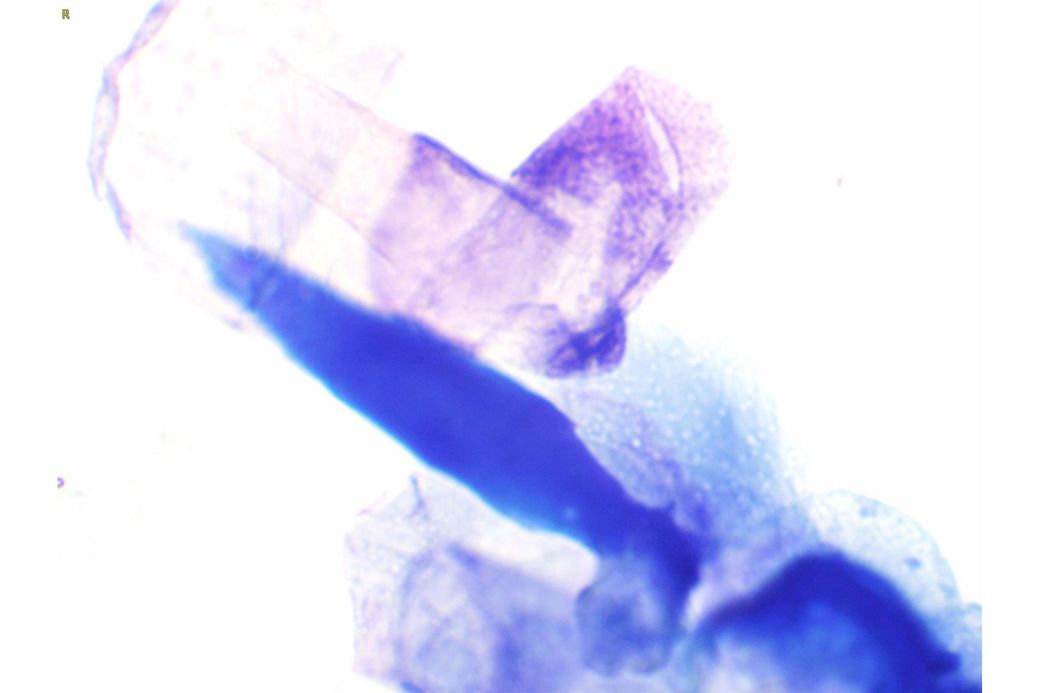

오늘 낮과 방금 5분전에 일어난 일인데요.. 강아지 귀질환 중에.. 옷입히고나서 귀를 바닥에 대고 비비거나, 귀에 통증을 호소하면서 잠깐 비틀비틀 걷는 경우 이런 경우 대체 뭘까요? 외이염일때도 이럴수도 있을까요? 아니면 중이염 내이염일지.. 한 2~3분정도 통증을 호소하다 지금은 또 정상이 됬는데 옷입을때만 옷의 목카라 부분이 귀에 닿을때 문제가 되는 느낌입니다. 평상시엔 가끔 양쪽 귀를 긁거나 귀를 자주 터는 정도입니다. 특이사항은 오른쪽귀 솜 돌돌 말아 귀안에 넣어줘도 비명을 지르며 엄청 아파하는데(작년11월경) 왼쪽은 안아파합니다)

그리고 용종이라고 코멘트 달아주셔서 저 검이경 사진 찍은곳에 물어보니 용종은 아니라고합니다.

저 부분 용종 아니라합니다